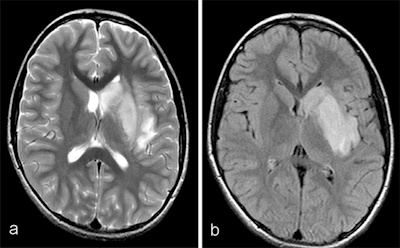

The child was diagnosed with COVID-19 disease via reverse transcription polymerase chain reaction (RT-PCR) testing; cerebrospinal fluid testing also produced positive results for SARS-CoV-2. Although a low-dose lung CT exam, a carotid color Doppler ultrasound, and echocardiography were all normal, MRI showed findings suggesting stroke.